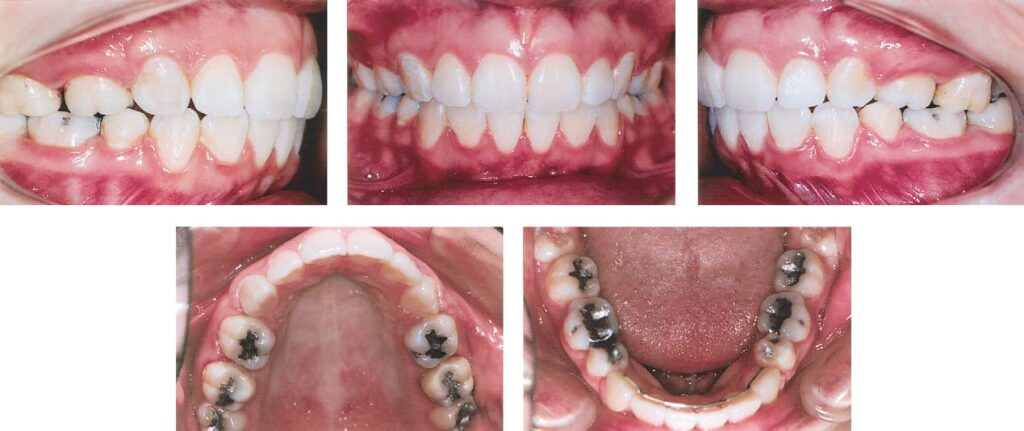

Fig 2. Intraoral photographs after incomplete treatment that included removing 4 first premolars.

A 23-year-old woman came for orthodontic treatment to the private orthodontic office of Dr M.R.J. Her major complaint was the persisting large overjet. She was undergoing orthodontic treatment with extraction of 4 first premolars to correct a Class II Division 1 malocclusion. Unfortunately, her treatment was not proceeding well because of her lack of compliance with headgear to reinforce anchorage. As a result, despite the extractions, she still had a significant overjet (Figs 1-3). There was no crowding, and the curve of Spee was mild. Because she was not satisfied with her progress at that stage, she abandoned treatment, with the orthodontic appliances still in place. One and a half years later, she decided to continue her treatment with Dr M.R.J. Cephalometrically, there was a severe Class II skeletal relationship with compensating maxillary and mandibular incisor tipping. The soft tissue profile was convex with a retruded mandible and chin (Fig 4 and Table). However, the patient said nothing about these characteristics. Radiographically, the maxillary third molars were in a favorable position functionally, but the mandibular third molars were not. Because of the previous unsuccessful orthodontic treatment, the maxillary incisors already had significant root resorption (Fig 5). There were no signs of active periodontal disease.